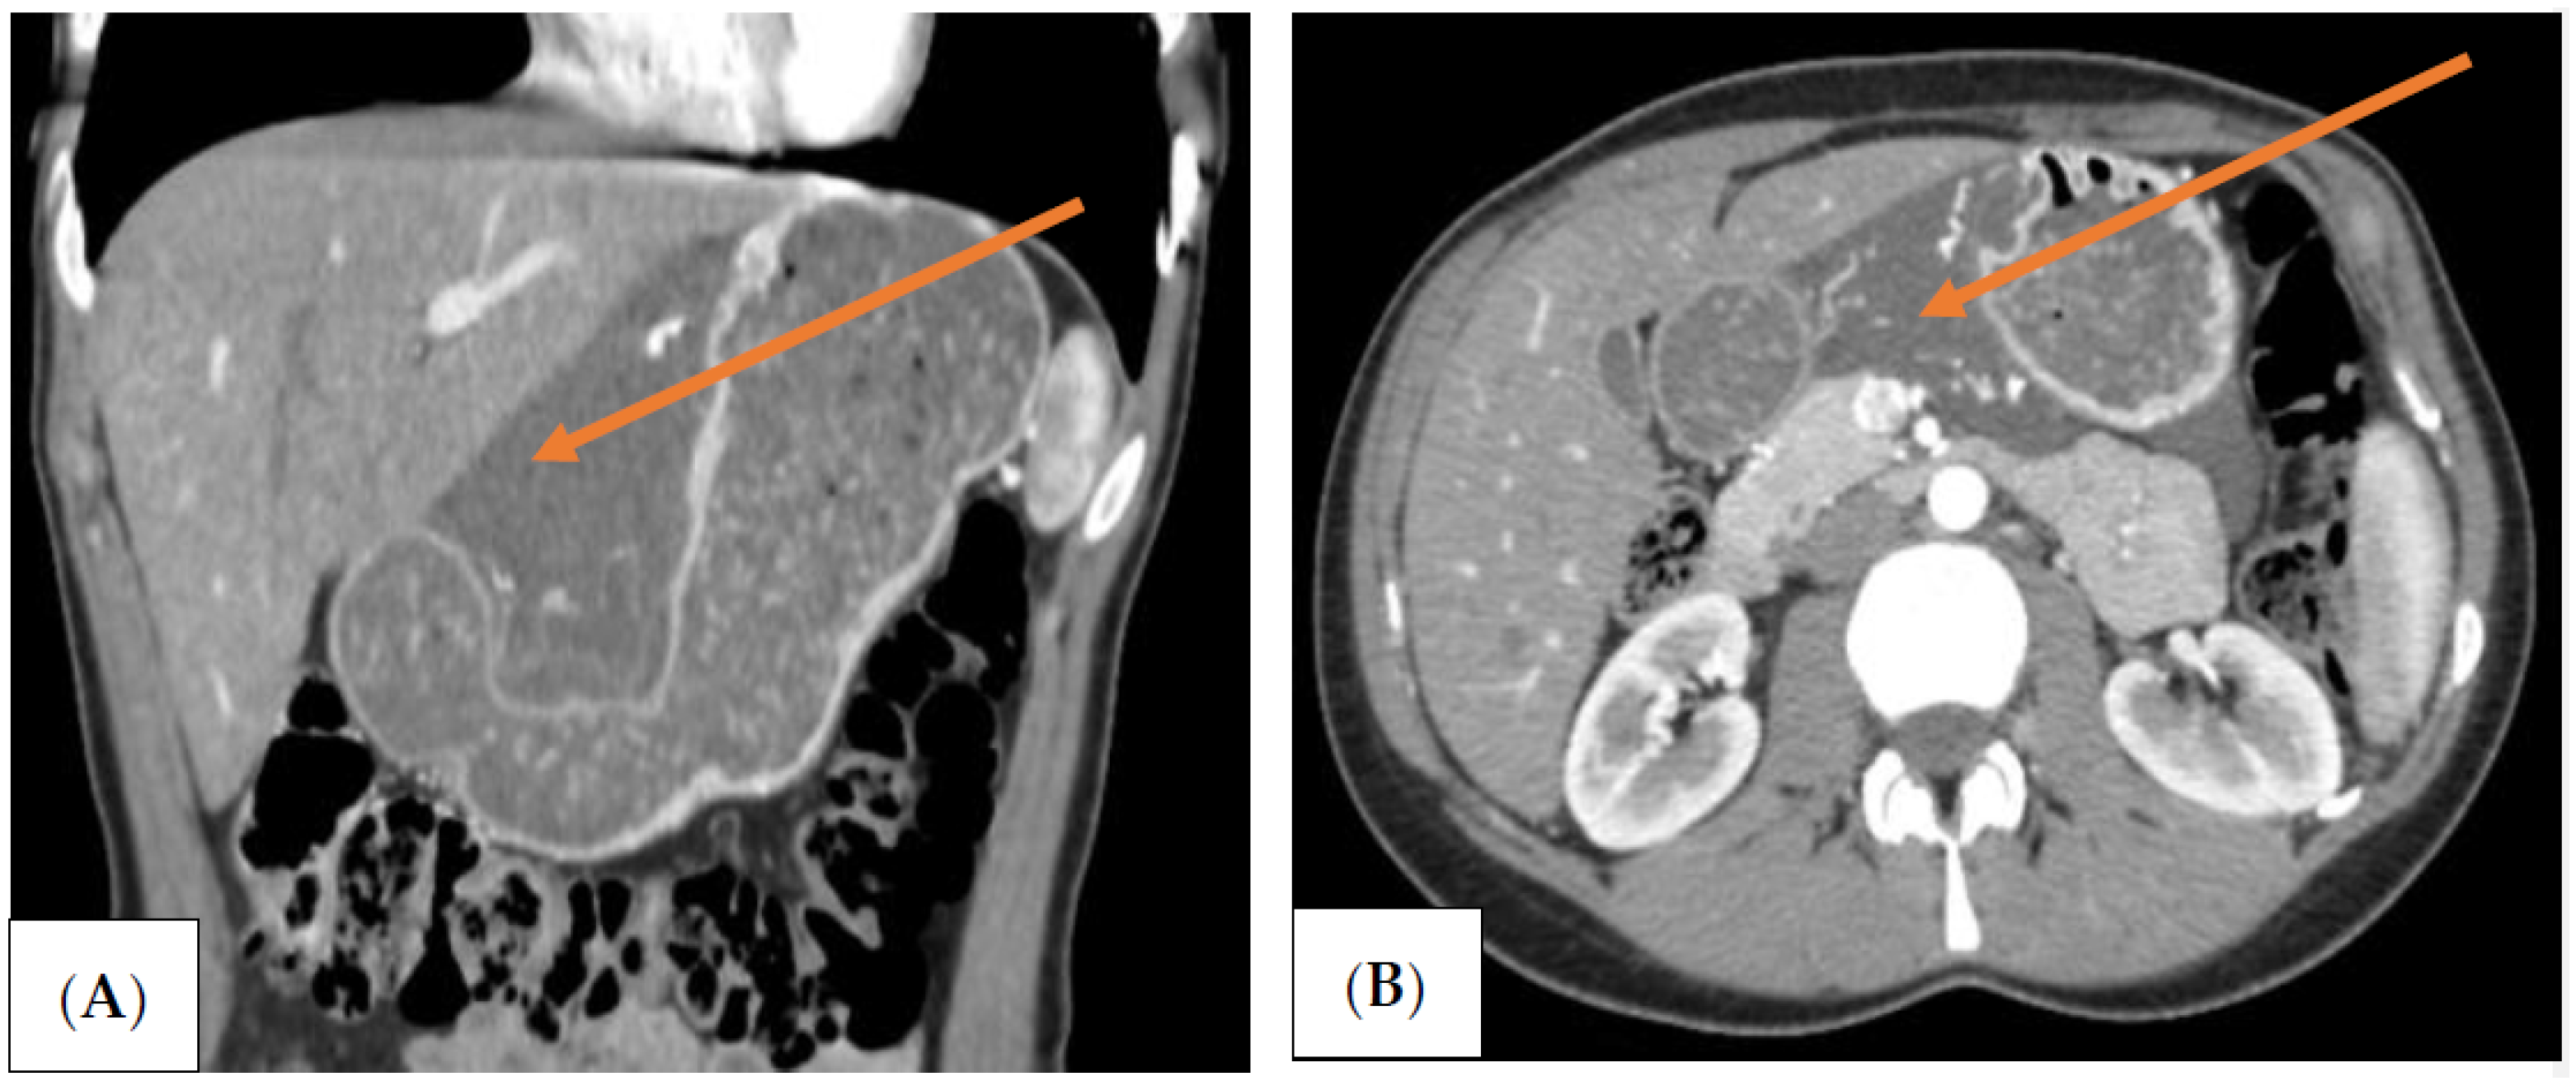

The patient was qualified for elective surgery. The presence of an approximately seven-cm long soft tissue extending along the lesser curvature of the stomach, closely connected to the stomach wall, was found intraoperatively (Figure 2). The tumour penetrated the gastrohepatic ligament, but did not reach the liver. The lesion did not penetrate the retroperitoneal space or infiltrate the pancreas. The tumour was completely removed without gastric wall resection (Figure 3). After removal of the lesion, the serosa of the lesser curvature of the stomach was secured with a continuous PDS 4/0 suture (Figure 4).

On gross examination, the resected specimen had a non-encapsulated, spongy, focally gelatinous mass measuring 7 × 5 × 2 cm. Microscopically, thin-walled, dilated vessels with different sizes, lined by a flattened endothelium without atypia (Figure 5A,B), and predominantly lymphatic in origin were observed (D2-40+, CD31+, CD34+, factor VIII+) (Figure 6A–C). Their lumina mostly contained proteinaceous fluid, with occasional admixture of lymphocytes, both B (CD20+) and T (CD3+) cells, histiocytes (CD68 KP1+), and erythrocytes, without plasma cells (CD138−, IgG4−). Larger lymphatic vessels with a layer of smooth muscle were also visible. Small lymph nodes with a preserved architecture (CD20, CD3, BCL6, CD23) and sinus dilatation were prevalent, as well as numerous smaller clusters of B and T lymphocytes (Figure 5B). Focal interstitial fibrosis and thickening of the connective tissue septum with myofibroblast proliferation were observed (SMA) (Figure 6D). The tumour focally surrounded normal blood vessels and nerve bundles and penetrated the adjacent adipose tissue, but not the stomach wall. The patient was diagnosed with a lymphangioma cavernosum.

Figure 3. The excised specimen following the operation. The size of the specimen is 7 × 5 cm.